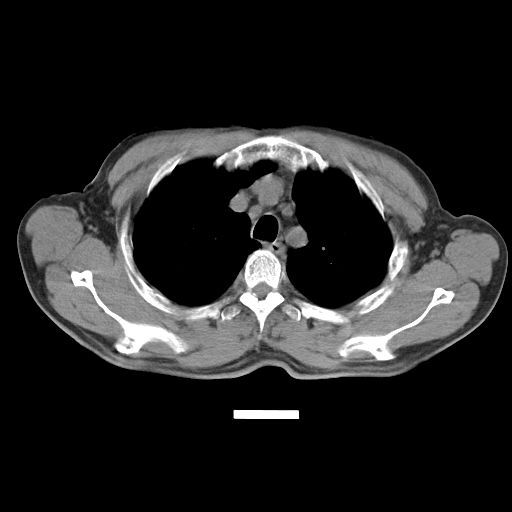

以下是引用心路寻觅在2010-3-1 10:23:00的发言:[br]1、考虑左肺上叶周围型肺癌[br]2、右上肺陈旧性病灶。[br][br][本贴已被 心路寻觅 于 2010-3-1 10:40:18 修改过]

以下是引用shuiyuan在2010-3-1 10:45:00的发言:[br]考虑左肺上叶中心型肺癌伴阻塞型炎症,邻近胸膜受侵。